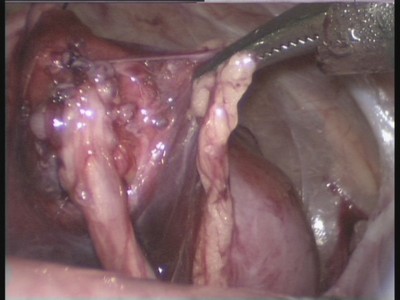

12. ábra. A laparoszkópiás műtét.

14. ábra. Megjelenés képződik anastomosis húgyvezeték medence